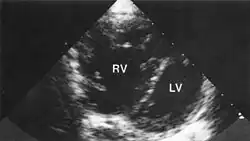

По мере прогрессирования у больных лёгочным сердцем наступают сдвиги кислотно-щелочного состояния, которые первоначально компенсированы, но в дальнейшем может наступить декомпенсация нарушений. Основными признаками лёгочного сердца являются увеличение размеров правого желудочка и изменения в крупных сосудах малого круга в виде переразвития мышечной оболочки, сужения просвета с последующим склерозированием. В мелких сосудах нередко обнаруживаются множественные тромбы. Со временем в увеличенном и изменённом миокарде развиваются дистрофические и некротические изменения.

В фазе компенсации клиническая картина характеризуется главным образом симптоматикой основного заболевания и постепенным присоединением признаков увеличения правых отделов сердца. У ряда больных выявляется пульсация в верхней части живота. Основной жалобой больных является одышка, которая обусловлена как дыхательной недостаточностью, так и присоединением сердечной недостаточности. Одышка усиливается при физическом напряжении, вдыхании холодного воздуха, в положении лёжа. Причинами болей в области сердца при лёгочном сердце являются обменные нарушения миокарда, а также относительная недостаточность коронарного кровообращения в увеличенном правом желудочке. Болевые ощущения в области сердца можно объяснить также наличием лёгочно-коронарного рефлекса вследствие лёгочной гипертензии и растяжения ствола лёгочной артерии. При исследовании часто выявляется синюшность.

Важным признаком лёгочного сердца является набухание шейных вен. В отличие от дыхательной недостаточности, когда шейные вены набухают в период вдоха, при лёгочном сердце шейные вены остаются набухшими как на вдохе, так и на выдохе. Характерна пульсация в верхней части живота, обусловленная увеличением правого желудочка.